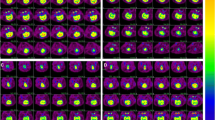

Absolute uptake values determined in PET-CT images analysis (Fig. 2) showed an increase in glucose uptake over time (Fig. 3). Data showed an exponential increase at the first 400 s of all measurements. In this part, the kinetics were almost the same, supported by a strong positive correlation R between baseline and PET scans post CA-CPR (WT, R = 0.986; TLR2−/−, R = 0.996). As well, no difference appeared in the kinetics of exponential glucose uptake in baseline PET scans over time among the mouse strains seen by a strong positive correlation (WT vs. TLR2−/−, R = 0.969). After the saturation of glucose uptake, the curve followed a linear course with a slight slope compared to the maxima (Fig. 3). The correlation coefficients displayed a strong positive correlation within the TLR2−/− animal group between baseline and PET scans post CA-CPR (R = 0.845), and in comparison with the baseline PET scans (WT vs. TLR2−/−, R = 0.961). In the WT animals, we found a moderate positive correlation in the curve progression (baseline vs. post CA-CPR, R = 0.162). The analysis of correlation shows that glucose uptake followed very similar kinetics over time in investigated groups and baseline and PET scans post CA-CPR.

When analyzing the last 15 min of measurement and plotted as absolute [18F]FDG uptake, a difference in quantity of glucose uptake could be revealed (Fig. 4). In Fig. 4a, the absolute uptake of [18F]FDG in the whole brain of every individual animal involved in data analysis is presented at baseline and post CA-CPR. In WT animals, 6/10 displayed an increase post CA-CPR, 1/10 showed reduced SUVmeans post CA-CPR, and 3/10 were at the same level with the SUVmeans. In contrast, the SUVmeans of all 10 TLR2-deficient animals displayed no differences between baseline and post CA-CPR uptake values. The absolute uptake of [18F]FDG in the whole brain was significantly higher in the group of WT animals post CA-CPR in comparison with baseline measurements (baseline SUVmean, 0.882 ± 0.055 vs. post CA-CPR SUVmean, 1.108 ± 0.021; n = 10, p = 0.017, r = 0.757 (large effect size), Fig. 4b). Approximately 140 min after CA-CPR, glucose uptake in the brain was increased by 25.6%. In contrast, the absolute glucose uptake in the whole brain of TLR2−/− mice was not significantly different between baseline and measurements post CA-CPR (baseline SUVmean, 1.187 ± 0.031 vs. post CA-CPR SUVmean, 1.120 ± 0.036; n = 10, p = 0.114, Fig. 4b). Hence, the different mouse strains presented a different pattern in glucose uptake at baseline and post-CPR.

Global cerebral metabolism measured using [18F]FDG-PET-CT and baseline regional [18F]F-FDG uptake in WT and TLR2−/− mice in absolute SUV. Absolute [18F]F-FDG uptake (SUVmean) in WT- and TLR2−/− mouse brain regions was measured at baseline and post CA-CPR (a, b). a SUVmeans of whole brain were presented for each animal as mean ± SD. b SUVmeans of whole brain for the groups of animals were shown as boxplots. * p value = 0.017 (Wilcoxon signed-rank test), # p value = 0.001 (Mann–Whitney U test). c The absolute [18F] FDG uptake values of baseline PET scans in WT(white)- and TLR2−/− (black) mouse brain regions displayed in comparison. Data shown as SUVmean ± SD; (p values WT vs. TLR2−/− mice): *1 0.000, *2 0.001, *3 0.002, *4 0.003, *5 0.005, *6 0.001, *7 0.001, *8 0.002, *9 0.009, *10 0.011, *11 0.002, *12 0.007, *13 0.000, *14 0.004.

In the WT animals, the absolute glucose uptake was increased post CA-CPR (Fig. 5a) in every brain region. Significant uptake increase was found in the basal forebrain, superior colliculi, inferior colliculi, hypothalamus, amygdala, midbrain, cerebellum, and brain stem. The increase of the SUV in the olfactory bulb, cortex, and striatum was not significant with a difference under 17%. The overall increase varied from 12.02% in the striatum and 42.04% in the hypothalamus (Fig. 5b).

Absolute regional cerebral metabolism measured using [18F]FDG-PET-CT. a and c Absolute [18F]F-FDG uptake (SUV) in WT (a) and TLR2−/− (c) mouse brains were measured at baseline and post CA-CPR. Data shown as SUVmean ± SD. a p values for WT (Wilcoxon rank-sum test): *1 0.017, *2 0.017, *3 0.017, *4 0.007, *5 0.017, *6 0.022, *7 0.013, *8 0.013. Because of Bonferroni correction hippocampus (p = 0.037), central gray (p = 0.028), and thalamus (p = 0.028) failed significance. c p values for TLR2−/− mice (Wilcoxon rank-sum test): *a 0.011, *b 0.011, *c 0.011, *d 0.021. Because of Bonferroni correction superior colliculi (p = 0.038) failed significance. b and d Percentage variation of absolute [18F]F-FDG uptake in baseline and post CA-CPR measurements in WT (b) and TLR2−/− (d) mice. Inset: Schematic representation of mouse brain regions subdivided in forebrain (red) and hindbrain (grey) (after 57): Bst brain stem, Cbm cerebellum, Ctx cortex, Hip hippocampus, Hyp hypothalamus, Mdb midbrain, Ofl olfactory bulb, Str striatum, Thl thalamus.

Unlike in the group of TLR2−/− mice, by trend, a decreased uptake of glucose post CA-CPR compared to the baseline measurements was noted. Significant differences were found in the olfactory bulb, cortex, striatum, and hippocampus (Fig. 5c). The decrease of glucose uptake was not significant with a difference of less than 9%, ranging from 13.91 (striatum) to − 1.22% (cerebellum).

When looking at the results of absolute data of investigated animal groups, apart from the fact that WT mice generally exhibited an increase and TLR2−/− a decrease of glucose uptake, the regions that were significantly different when comparing baseline and measurements post CA-CPR were partly opposite (Fig. 5a and c). Whereas in TLR2−/− mice, significant differences in forebrain occurred (see Fig. 5 red text and insert); this was not the case in the same brain areas of WT animals. In the WT group, significant differences were detected in the posterior cortical areas (= hindbrain; Fig. 5, insert).